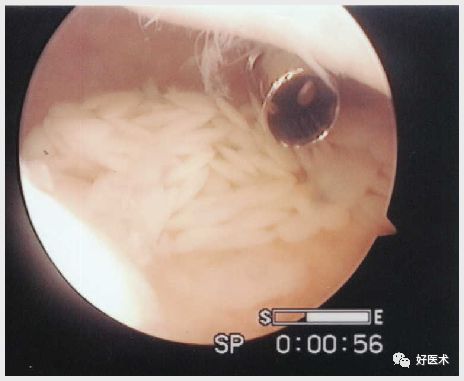

关节镜检查

受累关节均滑膜肥厚、充血、水肿、部分滑膜破裂在关节内呈纵形裂开、 肥厚 ,并有绒毛和皱襞形成;绒毛呈暗红色或棕黄色,长者如珊瑚状,短者增殖融合呈结节样变,直径1~3cm不等,亦呈红棕色或黄褐色,中老年人伴有不同程度软骨退变

关节镜下检查同时可以取滑膜组织进行病理检查